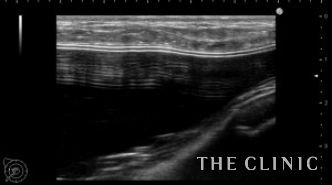

エコー所見です。

右はバッグの破損はありません。左はカプセル拘縮が強くエコーではカプセルとバッグの間に通常見られない組織を認めました。